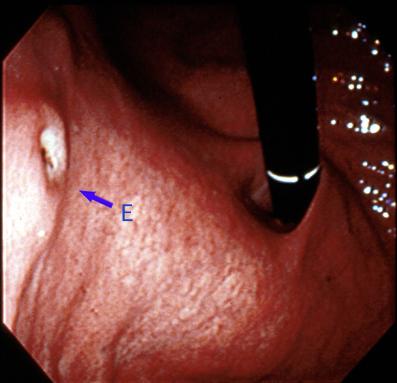

위에 다발병변을 나타낸 성인병 T세포백혈병(ATL)

[Image-ID:2035]

악성 림프계종양 및 혈액계종양/ATL(성인 T세포백혈병)

위(부위)/체부

0형(표재형)/IIa형(IIa+IIc)

20~24

sm